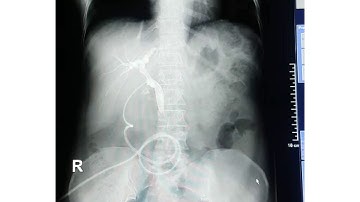

CHOLANGIOGRAM(T-TUBE) 🤔RADIOGRAPHY PROCEDURE // T-TUBE CHOLANGIOGRAM